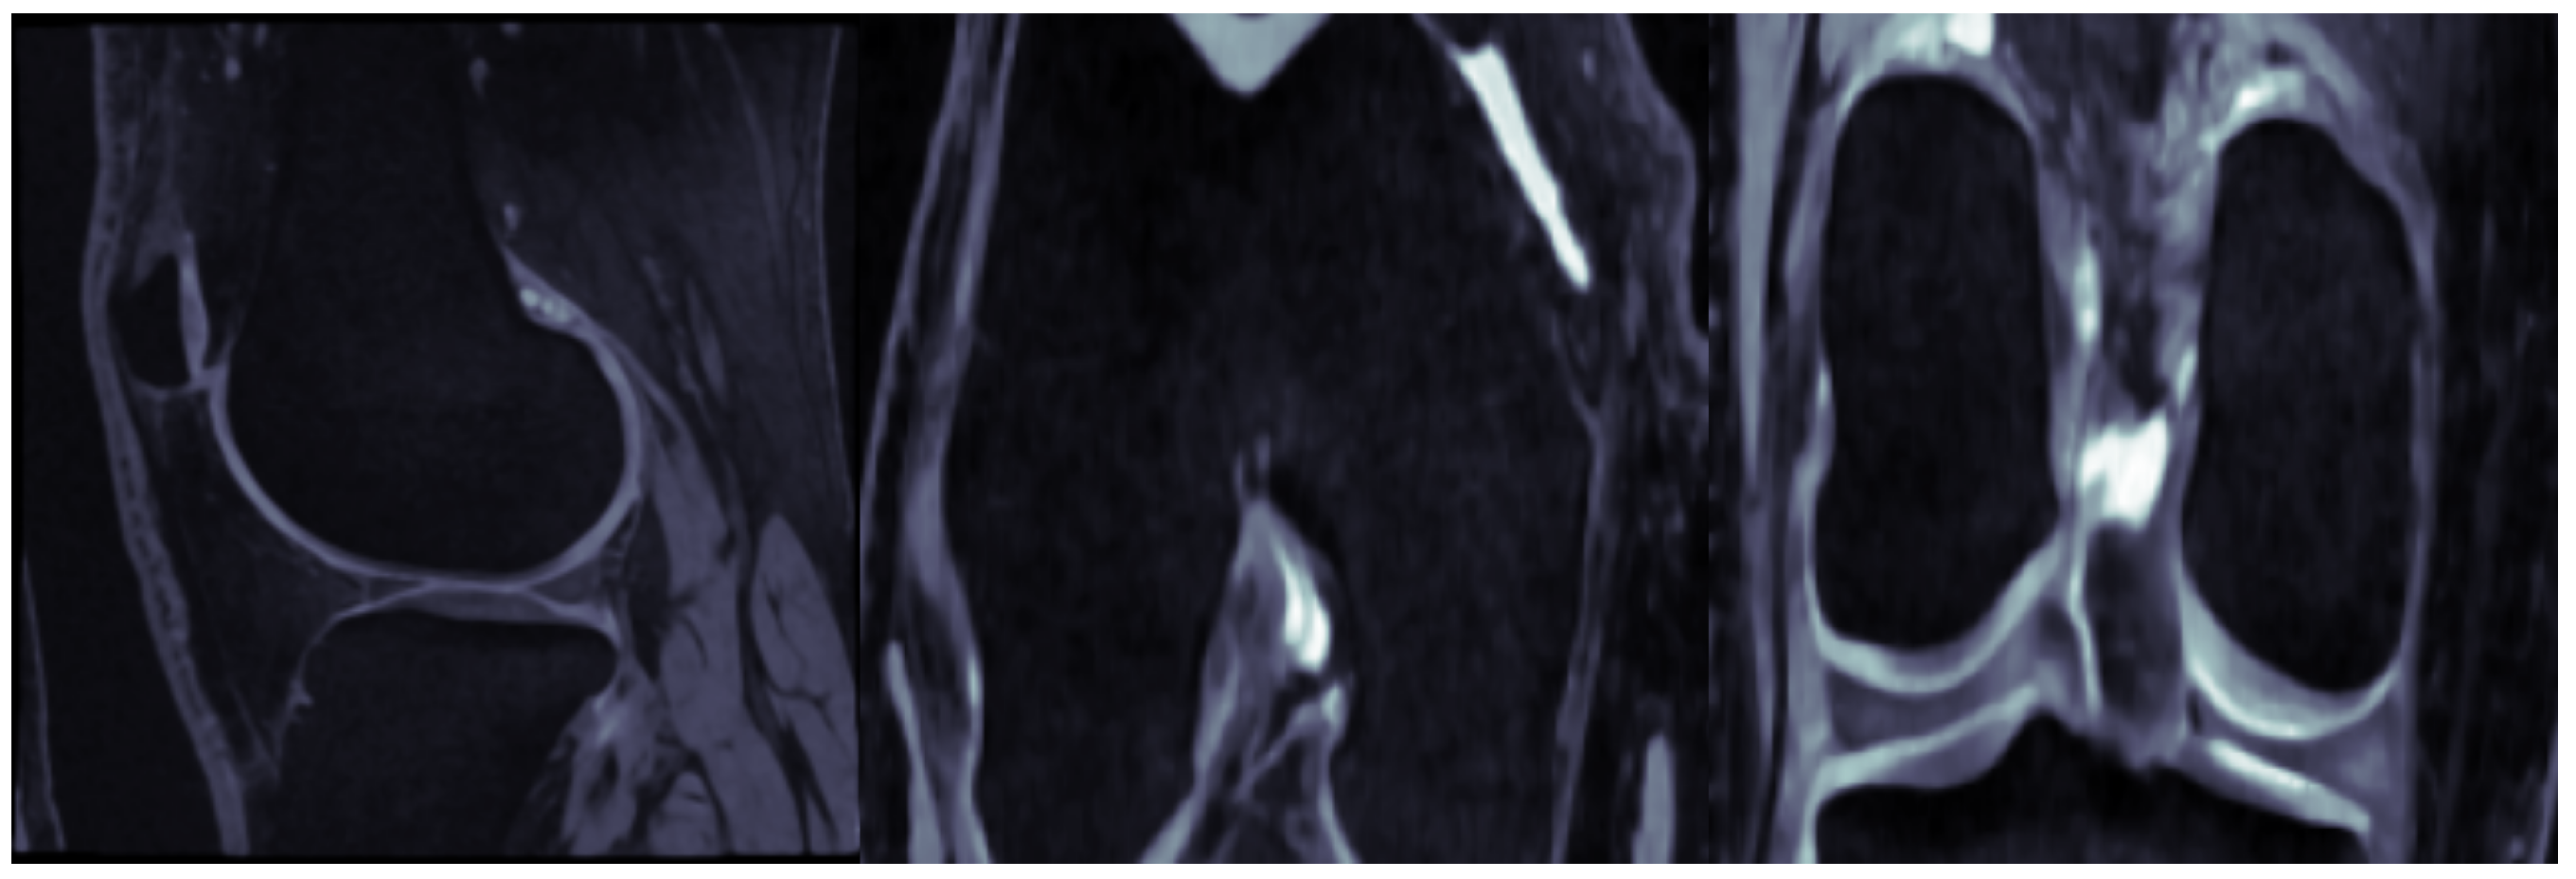

- Imaging biomarkers: Previous works in KOA analysis utilize a variety of imaging biomarkers as inputs to the risk models, such as the trabecular bone texture (TBT), hip -angle, knee alignment, medial and lateral osteophyte scores, and mainly, features detected by traditional CNNs [24]. In this work, we opt to utilize the 3D global shape descriptors extracted by the recently proposed C_Shape.Net [25] using 3D MR images. This is a deep hypergraph convolutional network, designed to model the structural properties of the 3D knee cartilage volume. C_Shape.Net operates on a hypergraph of volumetric nodes, which are formed from triangular surface meshes of the cartilage. Nodes are equipped with a rich set of local features, such as spatial and geometric features of the faces, as well as volumetric measures, including thickness and volume values. In that respect, 3D shape descriptors are tightly connected to the joint space width (JSW) at a particular time step. When considering JSW at the different time steps of a knee sequence, we can also detect the trends of joint space narrowing (JSN) over time, which provides important evidence for the assessment of KOA progression. At the input, we also use the injury history sequence, which may notably affect the progress of KOA disease.

8.8. Test Case Demonstration